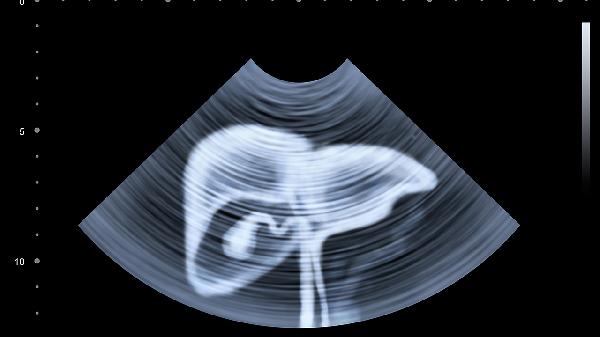

小儿腹部淋巴结13毫米×6毫米属于轻度增大,通常与感染或免疫反应有关,多数情况下无须特殊治疗。

儿童腹部淋巴结增大常见于病毒或细菌感染,如胃肠炎、呼吸道感染等。淋巴结作为免疫器官,在病原体刺激下可能出现反应性增生,表现为体积暂时性增加。该尺寸处于临界范围,若孩子无发热、持续腹痛、体重下降等症状,通常属于生理性反应。日常需观察孩子是否有食欲减退、活动力下降等表现,避免剧烈运动压迫腹部。饮食上可给予易消化的米粥、面条等,减少高脂食物摄入。保持充足休息有助于免疫系统恢复,建议每日睡眠时间不少于10小时。

若淋巴结持续增大超过15毫米或伴随长期低热、夜间盗汗,需考虑结核感染、淋巴瘤等疾病可能。这类情况需通过超声复查、血常规、结核菌素试验等进一步鉴别。恶性肿瘤引起的淋巴结肿大通常质地偏硬、活动度差,且增长迅速。家长发现孩子腹部触及明显包块或出现不明原因消瘦时,应及时到儿科或小儿外科就诊,通过增强CT或活检明确性质。